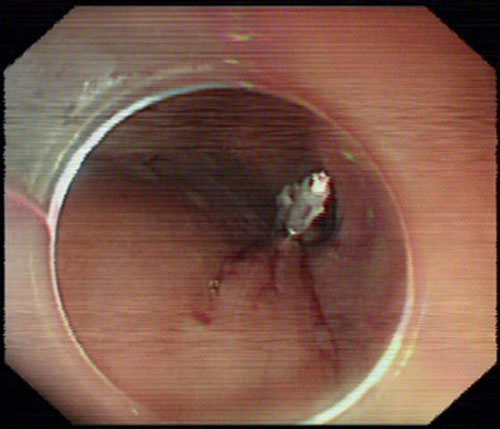

金属钛夹封闭隧道入口

2013年11月18日下午,经精心准备,在内镜中心麻醉呼吸机辅助全麻下,杨力主任运用内镜微创切除器械,于肿瘤上方5cm的食管黏膜纵向切开后,沿食管黏膜下层至肿瘤开辟了一条粘膜下“隧道”, 胃镜于“隧道”内直视下切除肿瘤,再用金属钛夹封闭食管表层的粘膜切口,历时65分钟顺利完成手术,术后第3天进流食,7天后患者康复出院,